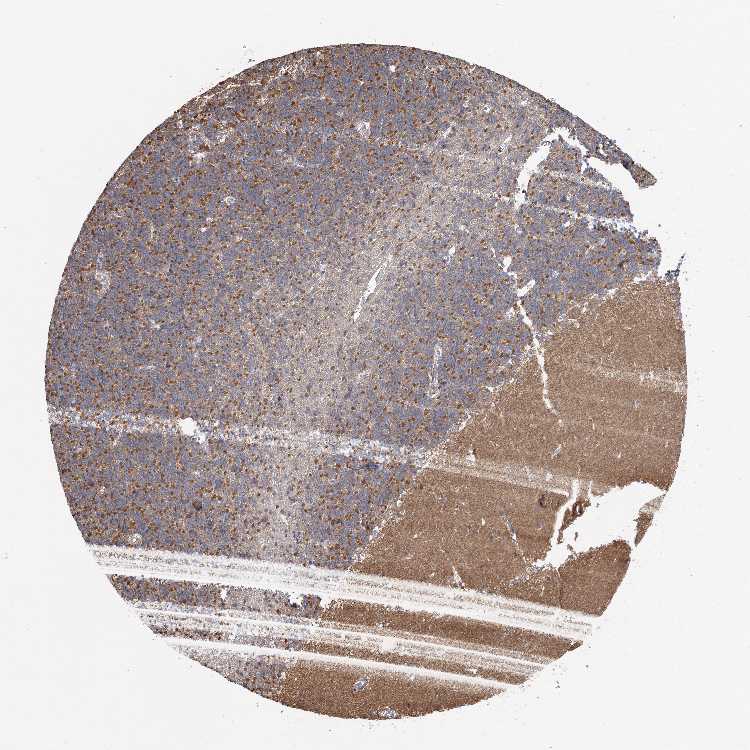

CEREBELLUM - Antibody stainingi

Antibody staining in the annotated cell types in the current human tissue is reported as not detected, low, medium, or high, based on conventional immunohistochemistry profiling in selected tissues. This score is based on the combination of the staining intensity and fraction of stained cells.

Each image is clickable and will lead to virtual microscopy that enables deeper exploration of all samples and also displays staining intensity scores, fraction scores and subcellular localization as well as patient and tissue information for each sample.

Antibody HPA036024

Purkinje cells Medium

Cells in granular layer Medium

Cells in molecular layer Not detected